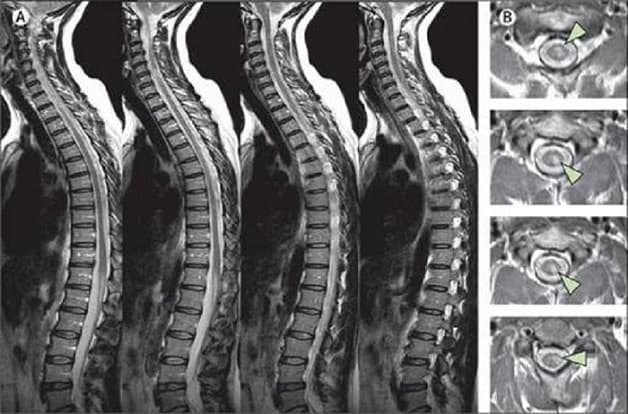

Hình ảnh thoát vị đĩa đệm và thoái hóa cột sống lưng qua chụp cộng hưởng từ MRI cột sống thắt lưng có thể giúp bác sĩ đánh giá vị trí tổn thương và giai đoạn tổn thương để có biện pháp can thiệp, điều trị hiệu quả.